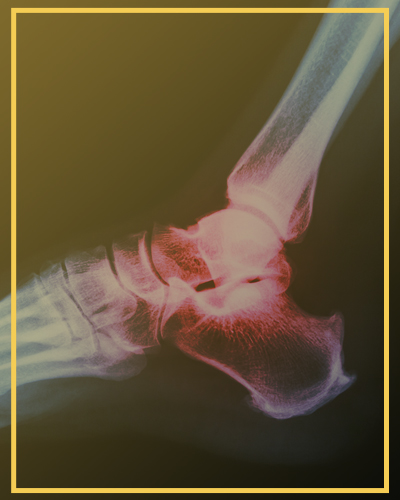

Fratura do Tornozelo

A fratura do tornozelo está entre as mais comuns dentro do trauma ortopédico.

Como ocorre a fratura do tornozelo? Basicamente, são dois mecanismos principais:

Torcional: conhecido como entorse ou torção, como ocorre comumente ao pisar num buraco ou ao desequilibrar na calçada.

Compressão Axial: ocorre nas quedas de altura em que o paciente cai de pé.

As fraturas por compressão axial são mais comuns em homens jovens (35 a 40 anos) e estão muito associadas a acidentes de trânsito e quedas de altura. Já a torção é mais frequente em mulheres mais velhas.

Os principais sinais e sintomas de fratura no tornozelo são: dor, edema (inchaço) e deformidade do tornozelo, além de incapacidade de apoiar o peso do corpo.

Em qualquer um dos mecanismos de trauma, ao apresentar sintomas, é fundamental ser avaliado por um ortopedista.